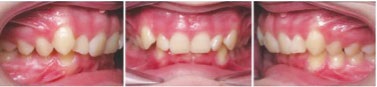

PATIENT INFORMATION:

• 14-year-old boy.

• Chief concern: overbite and crowding.

• Orthodontic diagnosis:

• Right side: Class II molar and canine (moderate).

• Left side: Class II molar and canine (severe).

• Overbite: severe deep bite.

• Upper arch: moderate crowding, with retroclined incisors.

• Lower arch: moderate crowding.

Figs. 3a-g: Initial records.